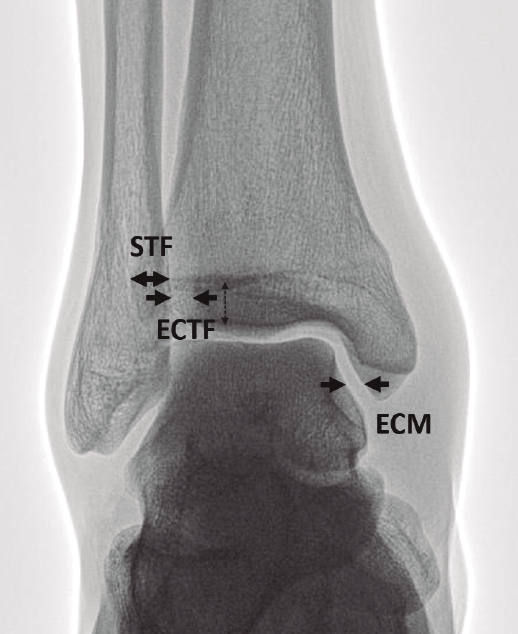

Figura 1. Parámetros radiográficos clásicos de sindesmosis estable en proyección anteroposterior (AP). ECM: espacio claro medial menor de 4 mm; ECTF: espacio claro tibiofifular menor de 6 mm; STF: solapamiento tibiofibular mayor de 6 mm.

En su artículo de 1989, Harper y Keller(11) establecieron los criterios radiográficos de una sindesmosis estable (Figura 1):

- Espacio claro tibiofibular (ECTF): distancia horizontal entre el borde lateral del maléolo posterior y el borde medial del peroné menor de 6 mm, tanto en la proyección AP como en la de mortaja.

- Solapamiento tibiofibular (STF): distancia entre el borde medial del peroné y el borde lateral del tubérculo tibial anterior mayor de 6 mm, un 42% del ancho del peroné en la proyección AP o mayor de 1 mm en la proyección de mortaja.

Las medidas son tomadas a 1 cm proximal del espacio articular del tobillo. - Espacio claro medial (ECM) ha sido otro parámetro habitualmente usado. Es la distancia entre el aspecto lateral del maléolo medial y el borde medial del astrágalo menor de 4 mm(12).

El rango de normalidad de estos parámetros tiene una amplia variedad en la literatura. No obstante, se debe destacar que ningún valor de medición considerado como normal se ha demostrado científicamente con claridad(13).

El ECTF ha sido usado largo tiempo apoyado en varios trabajos(14,15,16) y porque no cambia significativamente con la rotación(17,18). Sin embargo, la validez y fiabilidad de estos parámetros ha sido cuestionada por otros estudios en función de la amplia variedad anatómica y morfológica, la escasa fiabilidad inter- e intraobservador y la inexactitud por la posición del tobillo y su rotación(19).

Además, se ha publicado la escasa correlación de los valores estándar del ECTF y el STF con las lesiones de sindesmosis detectadas por resonancia magnética (RM)(20,21).

Por estas razones, sobre todo en lesiones sutiles, se recomienda la comparación del ECTF con el lado sano. Una diferencia de al menos 2 mm en esta medida es un hallazgo sugestivo de lesión sindesmal(5,10,16). No existe consenso acerca del valor diagnóstico del STF(21). El ECM está íntimamente relacionado con la incompetencia del ligamento deltoideo y, en consecuencia, de la sindesmosis, si se acompaña de una clínica sugestiva(22,23).